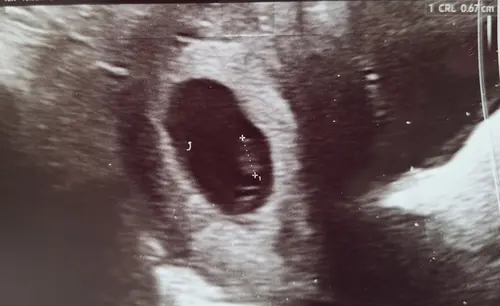

Ongeveer 5w5d en een kloppend hartje 🥰